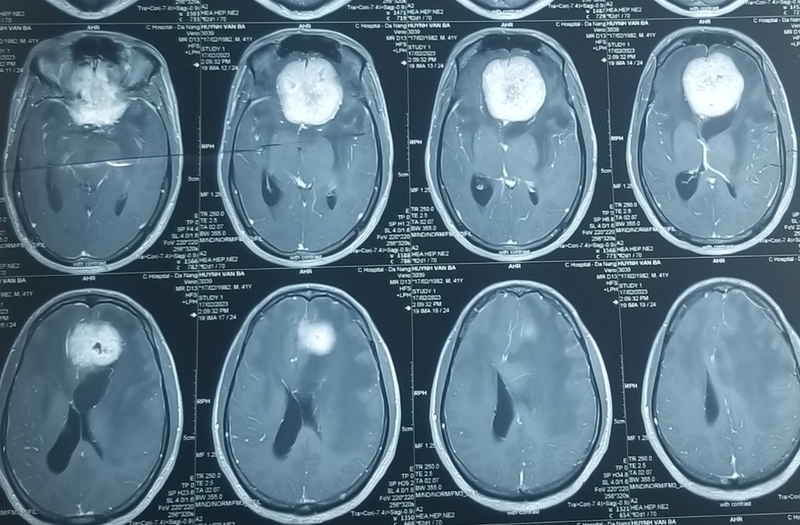

Não bộ được bao bọc bởi màng não gồm ba lớp là màng nhện, màng mềm và màng cứng. U màng não là một loại u phát triển từ các tế bào mũ của màng nhện trong não, đây là một lớp màng mỏng như mạng nhện phủ lên các nhu mô não và tủy sống.

Khối u màng não thường có tốc độ phát triển chậm, dấu hiệu u màng não thường diễn ra rõ ràng khi kích thước của khối u quá lớn. Một số khối u màng não không gây ra xuất hiện triệu chứng nào cho đến khi được chỉ định chụp CT scan não vì một triệu chứng não đó không liên quan. Các triệu chứng và dấu hiệu u màng não biểu hiện ra ngoài sẽ phụ thuộc vào kích thước cũng như vị trí của khối u.

Mặc dù tốc độ phát triển của u màng não là chậm và không xâm lấn, tuy nhiên khi khối u phát triển đến một kích thước đủ lớn có thể gây chèn ép vào các nhu mô não, rễ thần kinh. Từ đó gây rối loạn vận động, yếu liệt nửa người bên đối diện hoặc rối loạn thị giác nếu khối u nằm ở vùng rãnh thị giác, rối loạn tri giác…